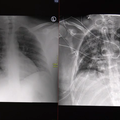

Rentgenska slika pljuč

UKC Ljubljana

Video: Strašljive posledice, ki jih povzroči covid-19

Dva primera covid pljučnice - pri enem bolniku se je stanje relativno hitro izboljšalo, drugemu, le 30-letnemu bolniku,…